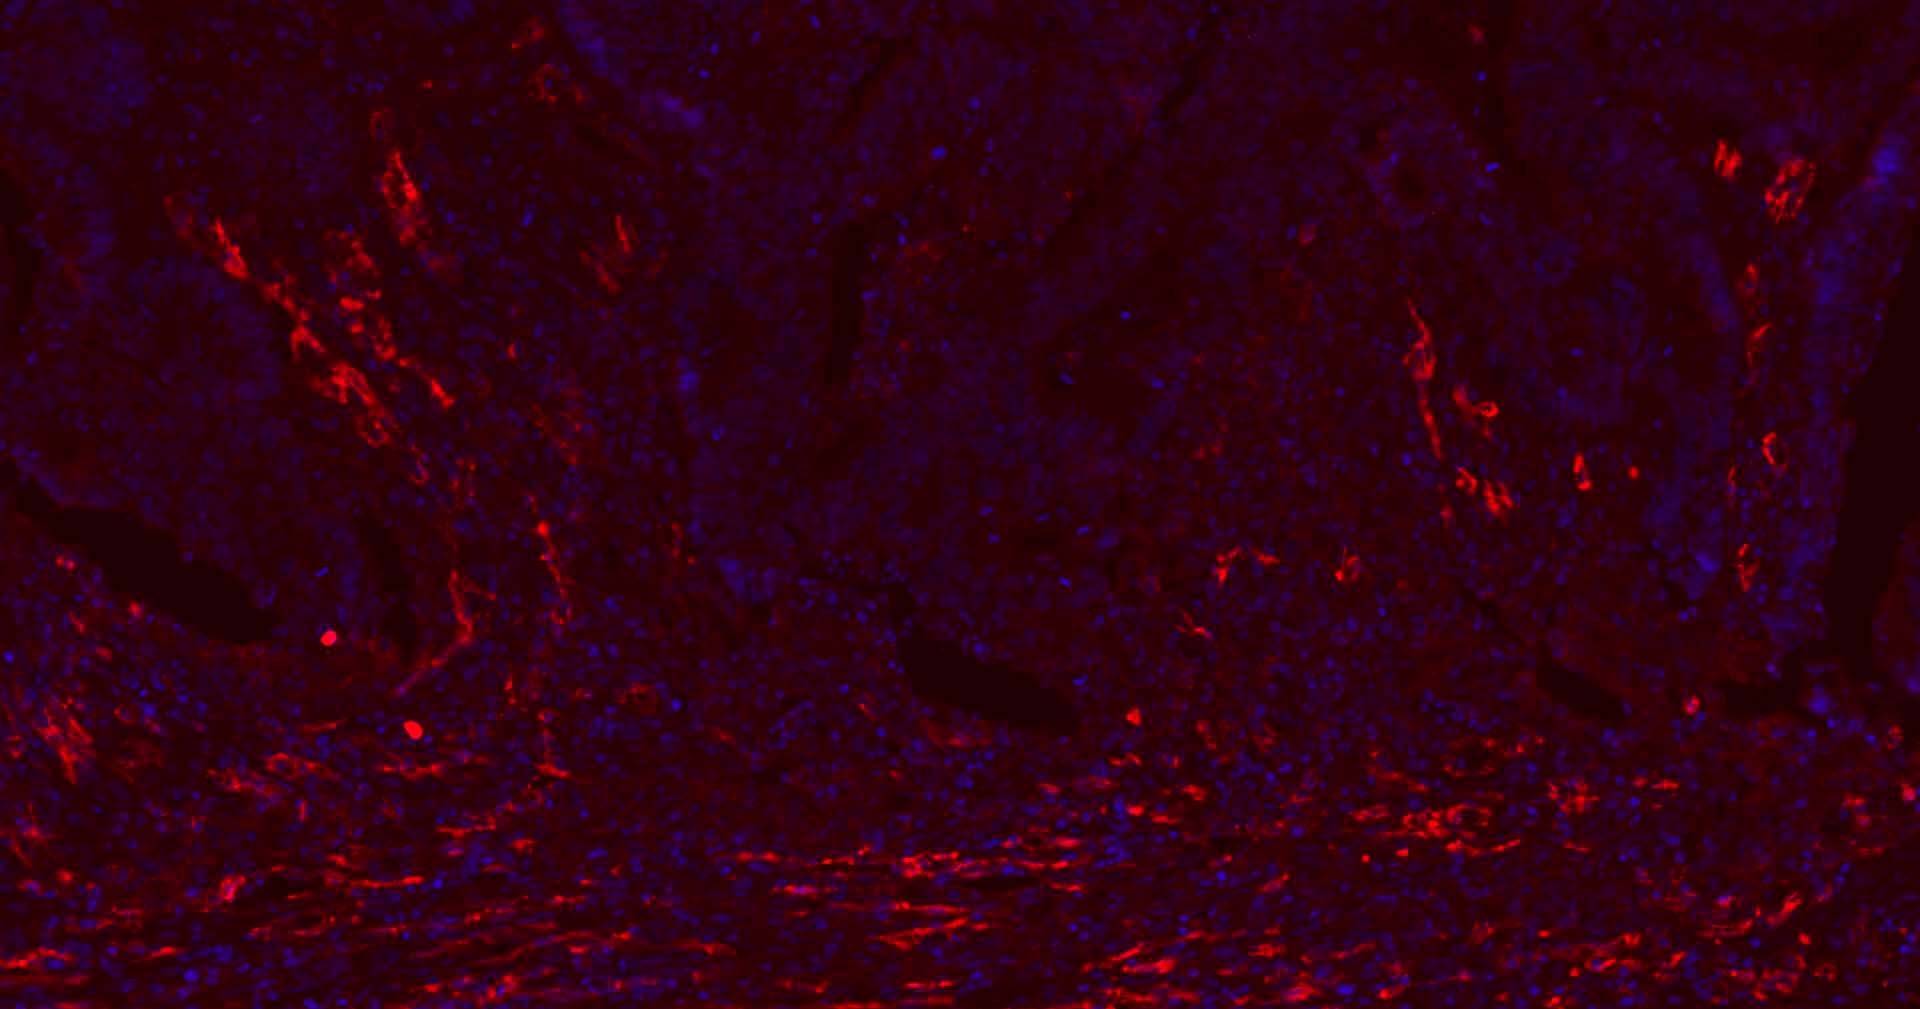

Paraformaldehyde-fixed, paraffin embedded Human Liver Cancer; Antigen retrieval by boiling in sodium citrate buffer (pH6.0) for 15 min; Antibody incubation with CD31 Monoclonal Antibody, Unconjugated (bsm-10825M) at 1:200 overnight at 4°C. Followed by conjugated Goat Anti-Rabbit IgG antibody (Red, bs-0296G-BF594), DAPI (blue, C02-04002) was used to stain the cell nuclei.